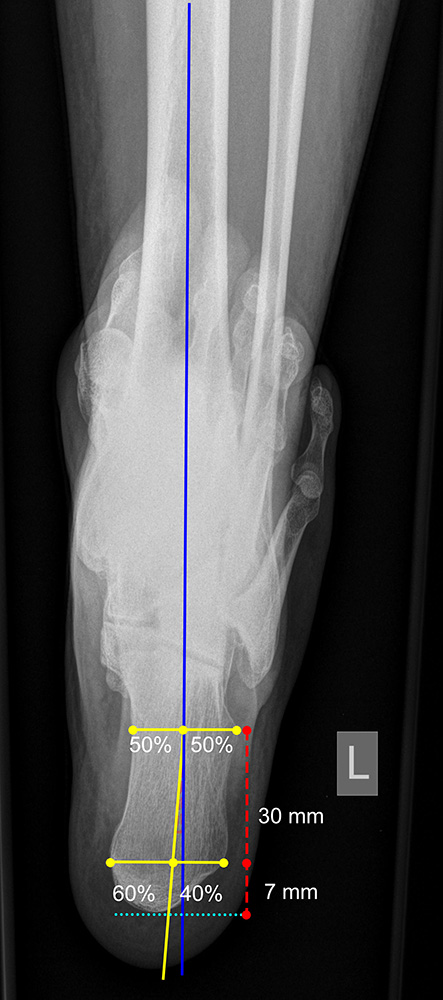

Long axial view

Indikation:

• Beurteilung der Rückfußachse.

Anmerkung:

• Auch der Long axial view ermöglicht eine Beurteilung der Stellung des Fersenbeins. Im Gegensatz zur Saltzman Aufnahme ist der Long axial view weniger anfällig für rotationsbedingte Fehlprojektionen 15

Positionierung:

• Der Patient steht beidbeinig mit gleichmäßiger Belastung auf beiden Füßen.

• Der zu untersuchende Fuß steht auf der Röntgenkassette.

• Die Röntgenkassette liegt horizontal am Boden.

• Der Zentralstrahl ist auf das obere Sprunggelenk fokussiert.

• Röntgenröhre wird 45° aus der Horizontalen nach plantar verkippt.

Kennzeichen des Röntgenbildes:

• Markieren der Tibiaachse mit Verlängerung nach distal.

• Kalkaneusachse: 7 mm distal des tiefsten Punktes des Kalkaneus wird eine horizontale Linie gezogen. 30 mm proximal davon wird eine zweite parallele Gerade durch den Kalkaneus gelegt. Die distale Linie wird im Verhältnis 40/60 medial/lateral geteilt. Die proximale Linie wird im Verhältnis 50/50 geteilt. Die Gerade welche beide Punkte verbindet ist die Kalkaneusachse.

• Die Rückfußachse im Long axial view ist definiert als Winkel zwischen Tibiaachse und Kalkaneusachse.

• Verläuft die Kalkaneusachse medial der Tibiaachse, handelt es sich um eine Varus-Stellung, verläuft sie lateral davon, um eine Valgus-Stellung.

• Norm: 2,1° 16.

Zur Vollansicht und zum Lesen der Bildbeschreibung bitte die Bilder anklicken.